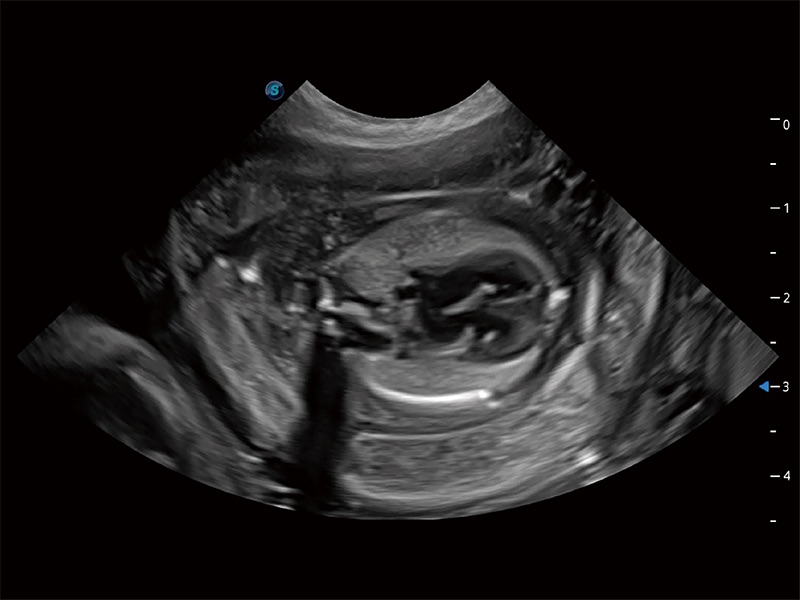

高性能和先进的临床应用工具可以为动物医生提供临床信心。ProPet 80 搭载了先进的腹部和浅表应用工具,帮助医生在日常临床实践中发挥前所未有的作用。

极大提升超低速微细血流的检出能力,同时更精准地滤除软组织和超声信号,为兽用医生提供以往无法通过常规血流获得的疾病诊断信息。

在传统二维血流成像的基础上,呈现血流的立体感,具有动感的生命力之美。即便是微小的血管也能轻松应对,提高了血流的视觉敏感性。